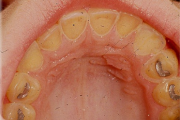

Tetratsükliini liigtarbimise tõttu värvunud hambad

Fluoroos

Fluoroosi

Hammaste defektid